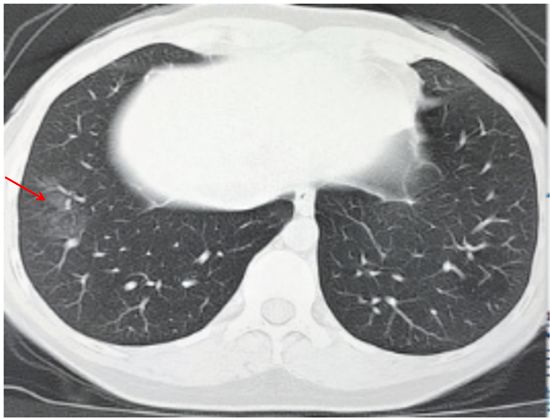

(一)病灶分布

病灶以肺外围背侧为主,以两肺下叶为著,与胸膜常紧贴,提示新冠肺炎病变多首先侵犯皮层肺组织的细支气管及肺泡上皮,病灶分布逐步从外周向中央扩展(图 2-1)

图2-1 早期病灶多数分布贴近胸膜(共4张)